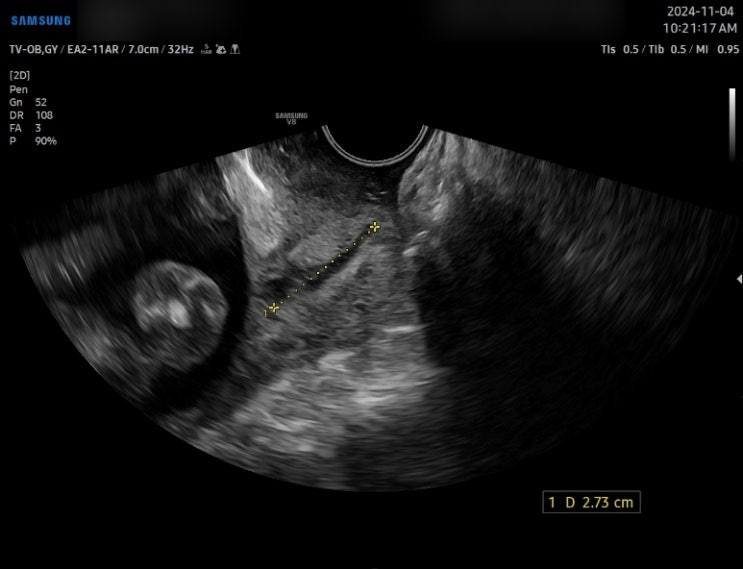

18주 임산부 자궁경부무력증(자궁경관무력증)으로 맥수술(맥도날드수술) 받은 후기 (1) / 큐트루

안녕하세요 큐트루예요. 18주 임산부 자궁경부무력증(자궁경관무력증)으로 맥수술(맥도날드수술) 받은 후기...